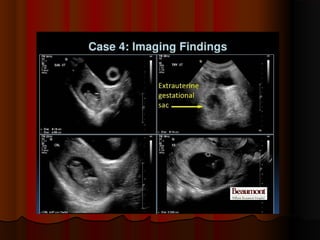

placental chorioangioma

 Sonography of the placenta in

Sonography of the placenta in

this 16 week pregnancy shows

a large, solid mass, that is non

calcific and shows mild

vascularity (vascular) and

excludes placental hematoma

excludes placental hematoma.

.

and shows many cystic spaces

within it

within it.

. This tumor of the

This tumor of the

placenta lies close to the cord

insertion site

insertion site.

. Ultrasound

Ultrasound

images of this type of placental

mass are highly suggestive of

placental chorioangioma.